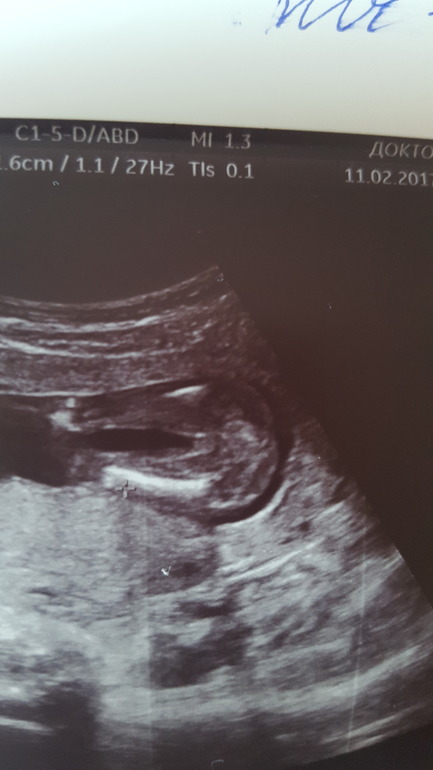

УЗИ, КТГ, доплерДевочки, милые!! Всем привет!!! Кто понимает посмотрите пожалуйста! сегодня поехали с мужем на узи узнать пол малыша, не дождавшись 2 скрининга. У нас уже 2 сыночка и очень хотели узнать кого ждем. Надеемся что доченьку! Узистка долго разглядывала, но в итоге сделала вывод что девочка. Но как-то неуверенно что ли.. сказала срок еще маленький (16-17 нед), но вроде ни яичек ни писюна не видит она. Муж уже скачет от радости, а у меня сомнения от ее неуверенности .

Фото с видео

На девочку похоже, на 17-ой недели похожая фотография была, половые органы на таком сроке еще немного опухшие у девочки, но четко видно разделение на две половинки должно быть=)) На вашем фото плохо конечно все детали видно. А на счет неуверенности, на 17 недели нам тоже неуверенно сказали..предположили только..и на 21 предположили..на 25 сказали что точно..на 31 подтвердили что точно.